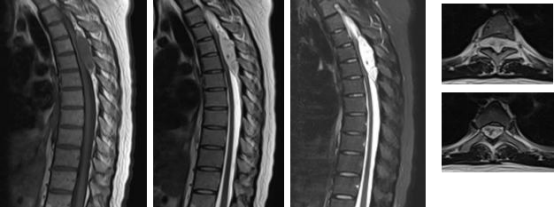

10月12日,剖宫产手术顺利完成,宝宝平安诞生。但抢救母亲的战斗才刚刚开始。剖宫产术后赵女士的神经症状仍在加重,双下肢已完全不能动弹。骨科团队第一时间介入。科室主任孙立组织全科讨论,全面评估病情与风险。最终决定由脊柱亚专业治疗组长、临床经验丰富、技术精湛的周焯家主任医师担任主刀,全力负责本次手术救治。周焯家细致查看患者并研判影像资料,明确诊断为胸椎硬膜外肿瘤压迫脊髓,必须尽快手术减压。经与家属充分沟通并取得支持后,救治进入关键阶段。于10月14日为赵女士施行“后路胸椎管内肿瘤切除+脊髓减压术”。术中发现肿瘤位于硬膜外,长度约10cm。凭借丰富的解剖知识与稳健的操作技巧,手术团队在保护脊髓和神经的前提下,将肿瘤完整剥离,彻底解除了压迫。